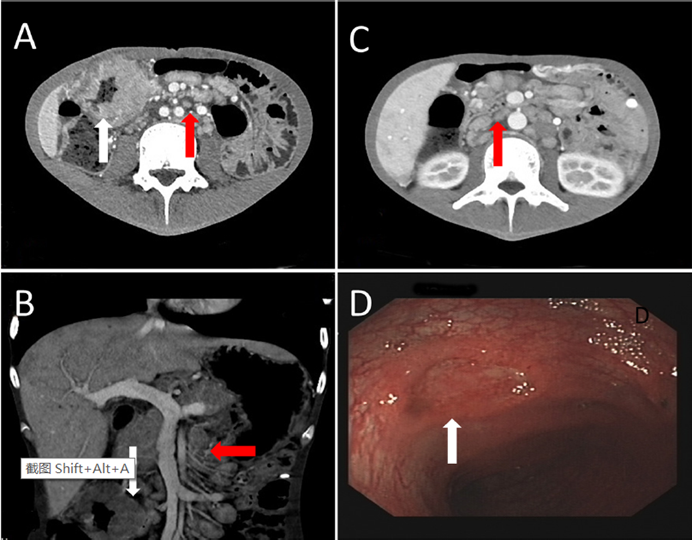

• 腹部增强CT显示淋巴结明显肿大,肠壁多处增厚,怀疑恶性淋巴瘤(图1.A、B、C)。结肠镜检查显示结肠多处溃疡(图1.D)

图1:腹部增强CT(A、B、C)显示明显的淋巴结肿大(红色箭头)和肠壁多处增厚(白色箭头)。结肠镜检查显示结肠多处溃疡(D,白色箭头)